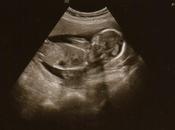

¿Qué es la restricción del crecimiento intrauterino?

Se denomina crecimiento intrauterino retardado o restricción del crecimiento intrauterino (RCIU), al retraso del crecimiento del futuro bebé cuando todavía... Leer el resto